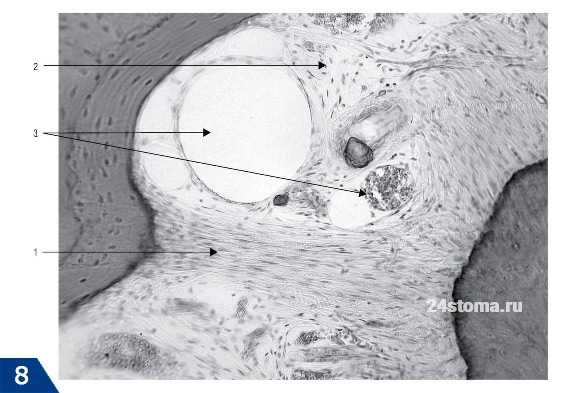

На рис.8 ниже вы можете увидеть коллагеновые волокна, проникающие в цемент корня. Обратим ваше внимание, что терминальные участки волокон (находящиеся в цементе корня или в костной стенке альвеолы) - называют шарпеевскими волокнами. Далее на рис.8 представлен гистологический препарат периодонта зуба, где 1 - пучки коллагеновых волокон, 2 - основное аморфное вещество, 3 - сосуды периодонта.